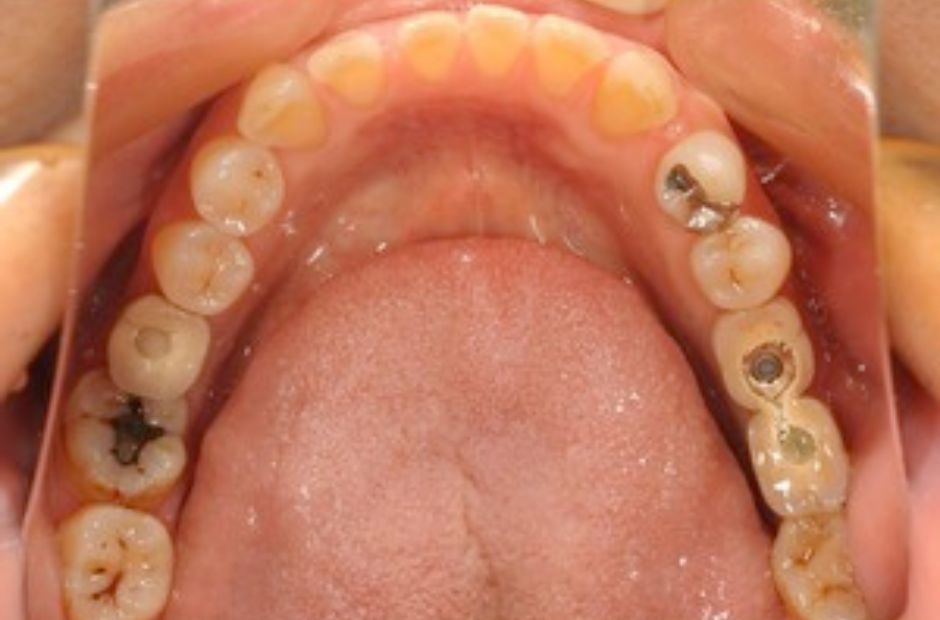

case.02

差し歯とインプラントの治療

若年の患者様が前歯の審美性について相談に来られました。差し歯とインプラントの組み合わせにより、自然で美しい笑顔を実現しました。患者様は見た目の改善と機能性の向上に大変満足されました。